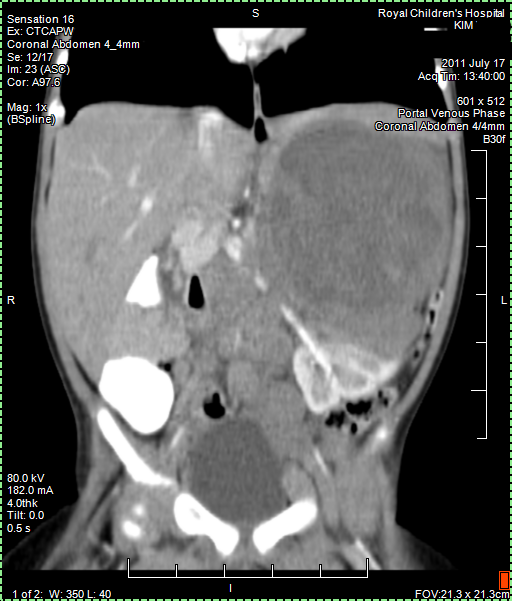

CT (CAT) scan 25 August 2011